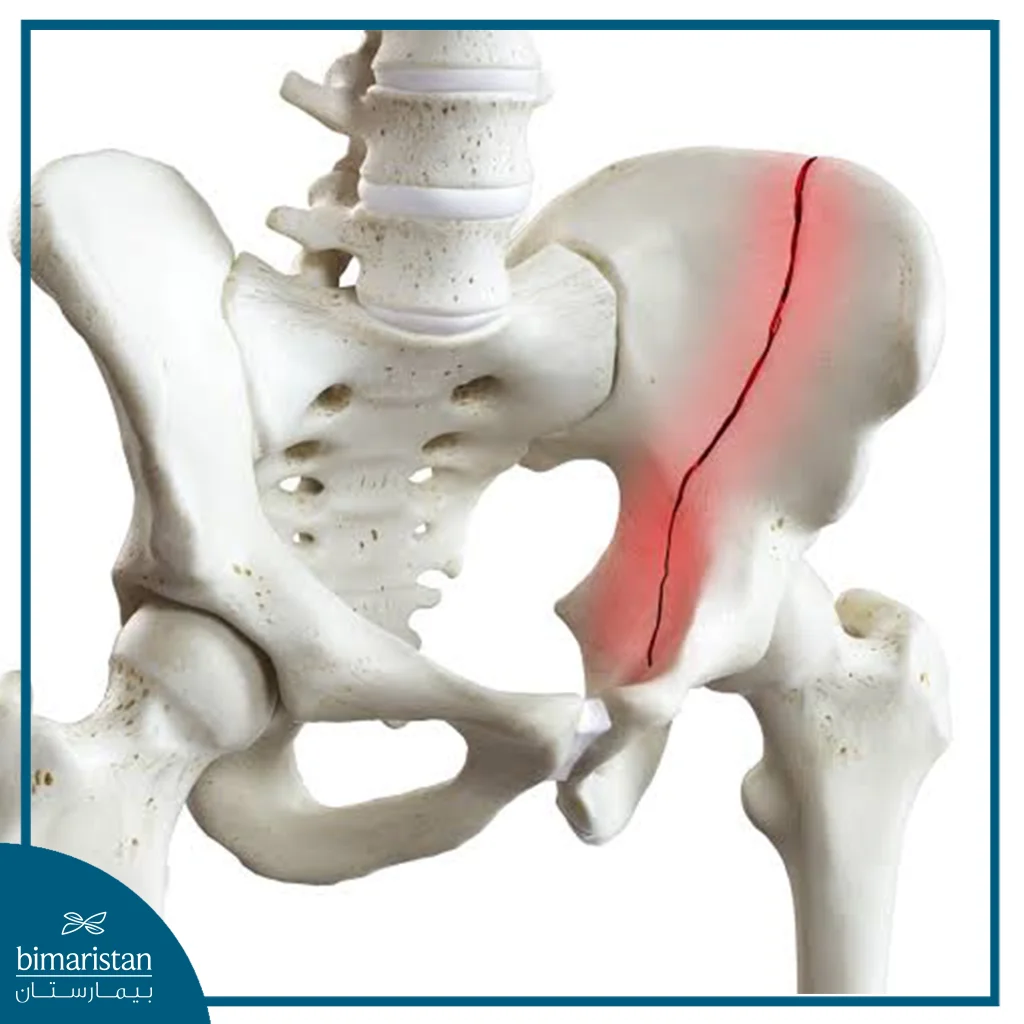

A pelvic fracture is a break in one of the bones that form the pelvic ring, which connects the spine to the legs and is an essential axis for supporting the body during movement, sitting and standing, as the fracture occurs when these bones are exposed to a force that exceeds their ability to withstand, whether as a result of a direct injury such as traffic accidents and falling from a height, or due to osteoporosis A pelvic fracture may range from a simple stable crack that does not change the location of the bones, to an unstable fracture in which the bones shift, causing damage to blood vessels or internal organs.

Pelvic fractures can be classified according to the fracture pattern into several main types, including closed or open fractures, complete fractures, displaced fractures, partial fractures, and stress fractures, and each type differs in the severity of its injury and the degree of pelvic stability after the fracture, and there is also another classification based on the stability of the fracture, where fractures can be classified into stable and unstable, which is an important classification to determine the treatment method and monitor recovery, the most important of these types:

Partial fractures involve cracks or fractures that do not extend across the entire bone, and are often more stable than complete or displaced fractures. Most of these fractures can be treated conservatively with a brace or temporary fixation, with careful monitoring to avoid the development of any complications.